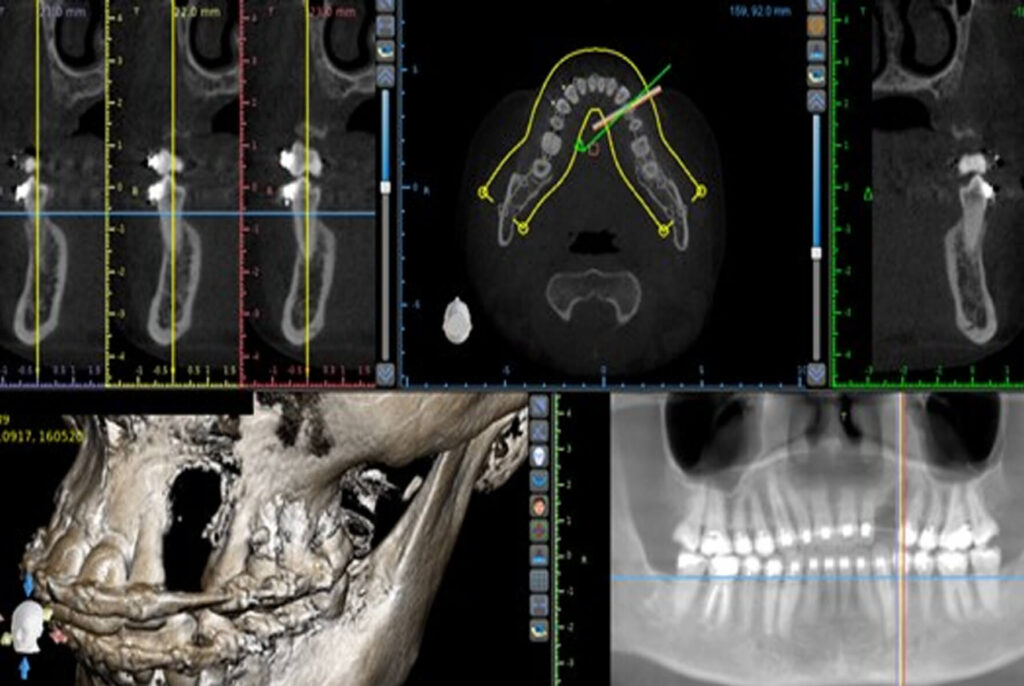

Reconstrução óssea tridimensional em regiãoposterior mandibular conforme a técnica de Khoury: 2 anos de acompanhamento

DOI: https://doi.org/10.71440/2675-5610.10.4.25.530-533.art Recebido: junho/2025 Revisado e aceito: julho/2025 Como citar:Barros LL, Urteaga VM, Salazar GB, Alberto W, Sá BCM, Skiba THI. Reconstrução óssea tridimensional em região posterior mandibular conforme a técnica de Khoury:2 anos de acompanhamento. ImplantNews 2025 Jul-Ago;10(4):530-3 1. Departamento de Implantodontia e Reabilitação Oral da SOEP – Porto Velho – RO Endereço correspondência:Lucas […]